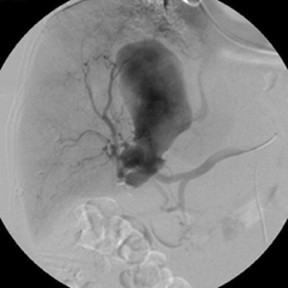

New study @AnnalsofIM bit.ly/2Km3KYu by @DrTalenfeld @WeillCornell: Percutaneous ablation for T1a #renalcancer has similar 5-year survival rates to radical nephrectomy but with far fewer 30-day complications and less #kidneyfailure.